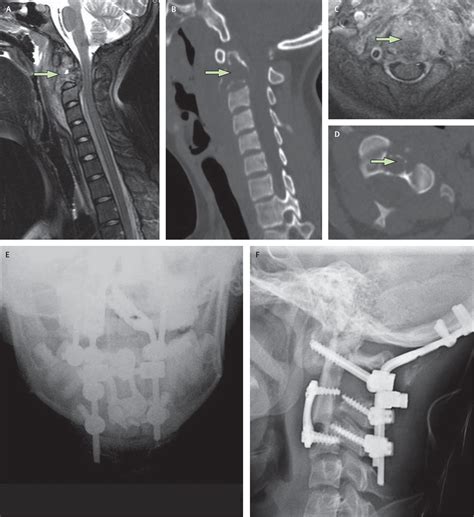

A spinal cord neoplasm is an abnormal growth of cells within or adjacent to the spinal cord. These growths can be classified based on their location: intramedullary (inside the spinal cord substance), extramedullary-intradural (inside the covering of the spinal cord but outside the cord itself), or extradural (outside the spinal cord covering, usually involving the vertebrae). Regardless of the location, these masses exert pressure on the delicate nerve fibers, leading to the clinical manifestations patients experience.

Once a physician suspects a spinal cord neoplasm based on the described symptoms, they will utilize advanced imaging to confirm the diagnosis. The goal is to identify the size, exact location, and potential nature of the growth. Magnetic Resonance Imaging (MRI) is the gold standard for evaluating spinal cord tumors because it provides high-resolution images of the spinal cord, nerve roots, and surrounding tissues.

In some cases, your medical team may suggest a contrast-enhanced MRI to better visualize how the tumor interacts with the spinal cord tissues. Additionally, if the symptoms are ambiguous, doctors might conduct an electromyography (EMG) or nerve conduction study to rule out other peripheral nerve conditions that mimic Spinal Cord Neoplasm Symptoms.